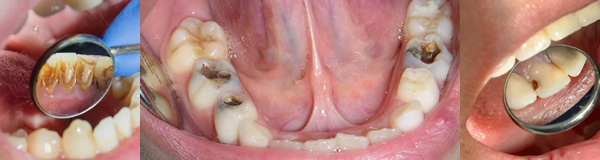

2. Experiencia de Caries Dental

La experiencia de caries hace referencia a la proporción de personas que, al momento del examen en el estudio, presentan evidencia de haber sufrido en algún momento de su vida, caries en alguna de sus fases.

Experiencia de caries dental (COP: cariados, obturados, perdidos) |

Dentición temporal |

Niñ@s 1 año= 6% |

Niñ@s 3 años= 47% |

Niñ@s 5 años= 62% |

Dentición Mixta |

Niñ@s 5-12 años= 60% |

Dentición permanente |

adolescentes 12 años= 54% |

adolescentes 18 años= 75% |

adultos 65 a 79 años= 96% |

Experiencia de caries dental (COP modificado: incluyendo estadio de caries incipiente) |

Niñ@s 1 año= 29% |

Niñ@s 3 años= 83% |

Niñ@s 5 años= 88% |

Niñ@s 5-12 años= 92% |

Adolescentes 12 años= 95% |

Adultos 65 a 79 años= 97% |